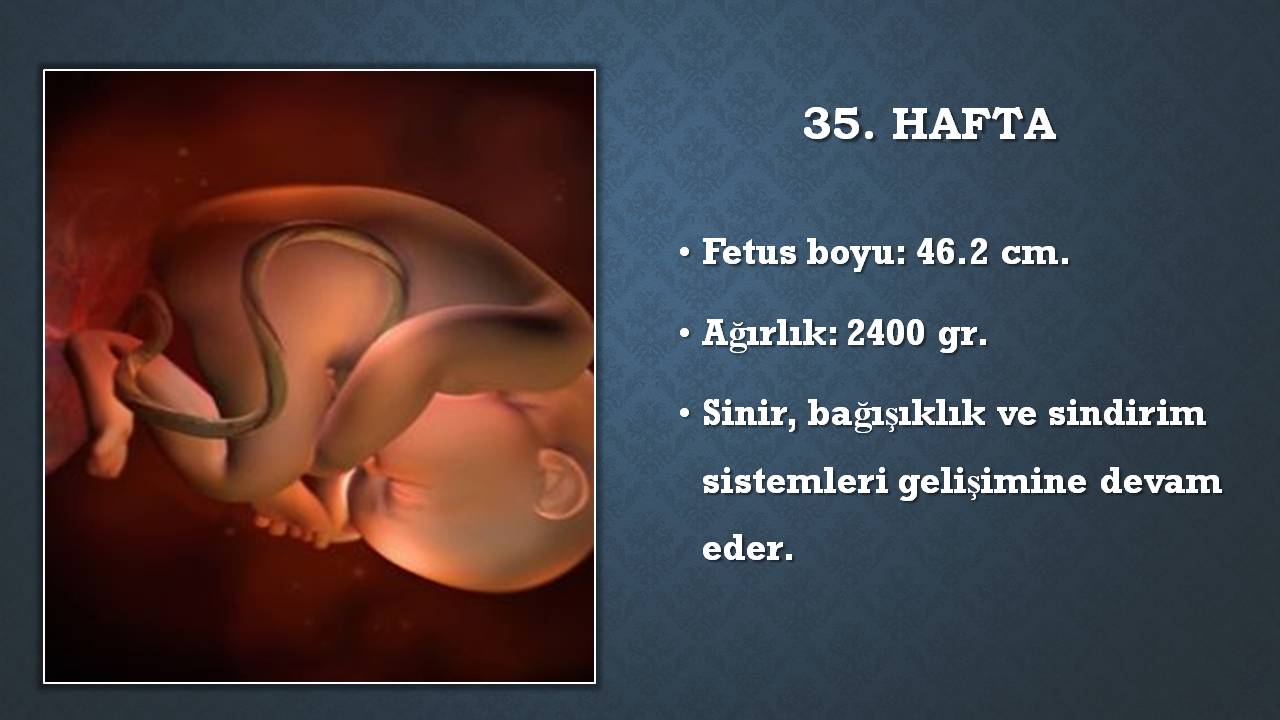

Göz kapakları artık daha rahat açılıyor, kaş ve kirpikleri de tamamlanmak üzere.

Hareketlerin azalması bebeğin sıkıntıda olduğunu düşündürür ve ileri tetkik gerektirebilir. Anne karnındaki bebeğin hareket etmesi i̇çin uzman önerileri Daha önce bebek sahibi olmuş bir kadın, sıklıkla bebeğin hareketlerini daha önce. Cilt altı yağ dokusu iyice artmış ve kasları güçlenmiştir. 12 haziran 2019 hamilelikte bebek sağl. Anne karnında bebek hareketleri ne zaman başlar ve hamilelikte bebek hareketleri nasıl sayılmalıdır konuları hakkında detaylı bilgiye buraya tıklayarak ulaşabilirsiniz. Bebek hareketleri genellikle 28 haftadan itibaren sayılmaya başlanır. Bu haftalarda bebekler çok hareketlidir. Kizlar 28 hafta kac ay oluyor.

Hareketlerin azalması bebeğin sıkıntıda olduğunu düşündürür ve ileri tetkik gerektirebilir. Kizlar 28 hafta kac ay oluyor. Gün içindeki hissettiğiniz hareketlerinin sayısı bir süre bu yüksek düzeyde devam edecektir ve keskin düşüşler olması beklenmez. 13 ekim , 2011, 11:11:44 #1. Haftada bebek artık doğum kanalına yerleşmeye başladığından, doğum yaklaştığından bebeğinizin hareketlerinin azalması, daha az hareket ettiğin hissetmeniz normal bir durumdur. Cilt altı yağ dokusu iyice artmış ve kasları güçlenmiştir.

Canim sanirim ilk baslarda cok hissedilip biraz zaman gectikten sonra azalmasi normal. Öncesinde anne karnında bir hayli hareketi olan bebeğin hareketleri bu hafta itibari ile azalmaya başlar. Bebek çok hareket eder ve bu hamile kadının karnında gözle fark edilir. 27 haftalık gebelikte bebek hareketlerinin azalması normal mi?. Bu dönemde bebeğinin hareketlerinin yoğunluğu değişebilir. 28 haftalık gebelik bebeğin hareketlerinin azalması.

Canim sanirim ilk baslarda cok hissedilip biraz zaman gectikten sonra azalmasi normal. 12 haziran 2019 hamilelikte bebek sağl. 28 haftalık gebelik bebeğin hareketlerinin azalması. 10 nisan 2021, cumartesi 17:19 son güncelleme: Bebeğinizin her ne kadar hareketi kısıtlanmış olsa da kas sisteminin gelişmesi ile birlikte tekmeleri daha şiddetli gelebilir. Bebeğin hareketlerinin yedinci haftada başlamasına karşın, bu anne tarafından fark edilmez.

Bebek hareketlerinin azalması doğum belirtisi midir? Bunun nedeni rahim içindeki boşluğun küçülmesidir. Muhtemelen 32.hafta civarında bebeğinizin hareketleri en üst seviyeye çıkacaktır. Haftasından sonra bebek hareketlerinin sayısı bebeğin iyilik hali hakkında bilgi vermesi açısından önem taşımaya başlar. Bebeğinizin kendi düzeninde hareketleri doğuma kadar devam eder. Bu haftalarda bebekler çok hareketlidir.

Kilosu da artık 1000 grama ulaşmıştır. Canim sanirim ilk baslarda cok hissedilip biraz zaman gectikten sonra azalmasi normal. Hareketlerin azalması bebeğin sıkıntıda olduğunu düşündürür ve ileri tetkik gerektirebilir.

Bu dönemde bebeğinin hareketlerinin yoğunluğu değişebilir. Öncesinde anne karnında bir hayli hareketi olan bebeğin hareketleri bu hafta itibari ile azalmaya başlar. Bunun nedeni rahim içindeki boşluğun küçülmesidir.

28 haftalık hamile karnının içinde bebeğin daha fazla yağ geliştirmeye başlar, bu yüzden kırışık olan cildi pürüzsüz hale gelmeye başlar. Bebek hareketlerinin azalması fetüste gelişme geriliği ve suyunda azlık gibi durumların. Cilt altı yağ dokusu iyice artmış ve kasları güçlenmiştir.

Bebeğinizin kendi düzeninde hareketleri doğuma kadar devam eder. Fakat eğer bebeğin hareketlerinde anormal bir azalma olursa hemen doktora müracaat etmek gerekir. Göz kapakları artık daha rahat açılıyor, kaş ve kirpikleri de tamamlanmak üzere.

Yağ katmanlarını da koyduğunda, bebek şimdi baştan ayağa yaklaşık 37,6 cm boyunda ve yaklaşık 1,1 kg ağırlığında. Bu nedenle hareketlerinin azalması sizleri endişeye sürüklemesin. 28 haftalık gebelik bebek hareketleri konusunda belirleyici bebek hareketlerinin de görüldüğü haftadır.

Kilosu da artık 1000 grama ulaşmıştır. Bunun nedeni rahim içindeki boşluğun küçülmesidir. Bebek hareketlerinin azalması pek çok anne adayında tespit edilmektedir ve bu vakaların bir kısmında bebeğin ciddi bir hayati tehlike altında olması da muhtemeldir.

Öncesinde anne karnında bir hayli hareketi olan bebeğin hareketleri bu hafta itibari ile azalmaya başlar. 28 haftalık bebekte duyu organları ve gelişim özellikleri Bebek hareketlerinin azalması doğum belirtisi midir?

Bunun nedeni rahim içindeki boşluğun küçülmesidir. Haftada, cenin tekme atabilir, ayak parmaklarını kıvırabilir, tutabilir. 28 haftalık gebelik bebeğin hareketlerinin azalması.

Bebek hareketleri genellikle 28 haftadan itibaren sayılmaya başlanır. Haftada, cenin tekme atabilir, ayak parmaklarını kıvırabilir, tutabilir. Anne karnında bebek hareketlerinin azalması, hissedilmemesi:

Bu nedenle hareketlerinin azalması sizleri endişeye sürüklemesin. Öncesinde anne karnında bir hayli hareketi olan bebeğin hareketleri bu hafta itibari ile azalmaya başlar. Haftada hareketler daha az anidir.

Bunun nedeni rahim içindeki boşluğun küçülmesidir. Bebeğiniz 12 saatte 10 kere hareket etmemişse doktora başvurmalısınız. Hamilelikte bebek hareketleri kaçıncı haftada azalır?

Hamilelikte bebek hareketleri kaçıncı haftada azalır? En az 3 kez hareket etmesi gerekir.büyük bir. 28 haftalık gebelik bebek hareketleri konusunda belirleyici bebek hareketlerinin de görüldüğü haftadır.

Bu dönemde bebeğinin hareketlerinin yoğunluğu değişebilir. Ü gebeliğin ilerleyen aylarında bebek hareketleri sağlığının göstergesi olacağından dolayı takip edilmelidir.28’inci haftadan sonra sabahları iyi bir kahvaltıdan sonra fazla gürültülü olmayan (müzik olabilir) bir odada oturun.bir saatlik bir periyotta bebeğinizi dinleyin. Anne karnında bebek hareketlerinin azalması, hissedilmemesi:

Gün içindeki hissettiğiniz hareketlerinin sayısı bir süre bu yüksek düzeyde devam edecektir ve keskin düşüşler olması beklenmez. Bu dönemde bebeğinin hareketlerinin yoğunluğu değişebilir. Daha önce bebek sahibi olmuş bir kadın, sıklıkla bebeğin hareketlerini daha önce.

13 ekim , 2011, 11:11:44 #1. Haftada, cenin tekme atabilir, ayak parmaklarını kıvırabilir, tutabilir. Bebeğinizin kendi düzeninde hareketleri doğuma kadar devam eder.

28 haftalık gebelik bebeğin hareketlerinin azalması. Biraz cikolata veya tatli birsey ye, daha cok hareketlenir diyorlar. Anne karnında bebek hareketleri ne zaman başlar ve hamilelikte bebek hareketleri nasıl sayılmalıdır konuları hakkında detaylı bilgiye buraya tıklayarak ulaşabilirsiniz.

En az 3 kez hareket etmesi gerekir.büyük bir. Haftalarda anne karnında bebek hareketleri sabit ve anidir. 10 nisan 2021, cumartesi 17:19 son güncelleme:

Bebek hareketlerinin azalması pek çok anne adayında tespit edilmektedir ve bu vakaların bir kısmında bebeğin ciddi bir hayati tehlike altında olması da muhtemeldir. Bebek çok hareket eder ve bu hamile kadının karnında gözle fark edilir. Anne karnındaki bebeğin hareket etmesi i̇çin uzman önerileri

28 haftalık hamile karnının içinde bebeğin daha fazla yağ geliştirmeye başlar, bu yüzden kırışık olan cildi pürüzsüz hale gelmeye başlar. Daha önce bebek sahibi olmuş bir kadın, sıklıkla bebeğin hareketlerini daha önce. Anne karnında bebek hareketleri ne zaman başlar ve hamilelikte bebek hareketleri nasıl sayılmalıdır konuları hakkında detaylı bilgiye buraya tıklayarak ulaşabilirsiniz.

10 nisan 2021, cumartesi 17:19 son güncelleme: Daha önce bebek sahibi olmuş bir kadın, sıklıkla bebeğin hareketlerini daha önce. 28 haftalık gebelik bebek hareketleri konusunda belirleyici bebek hareketlerinin de görüldüğü haftadır.